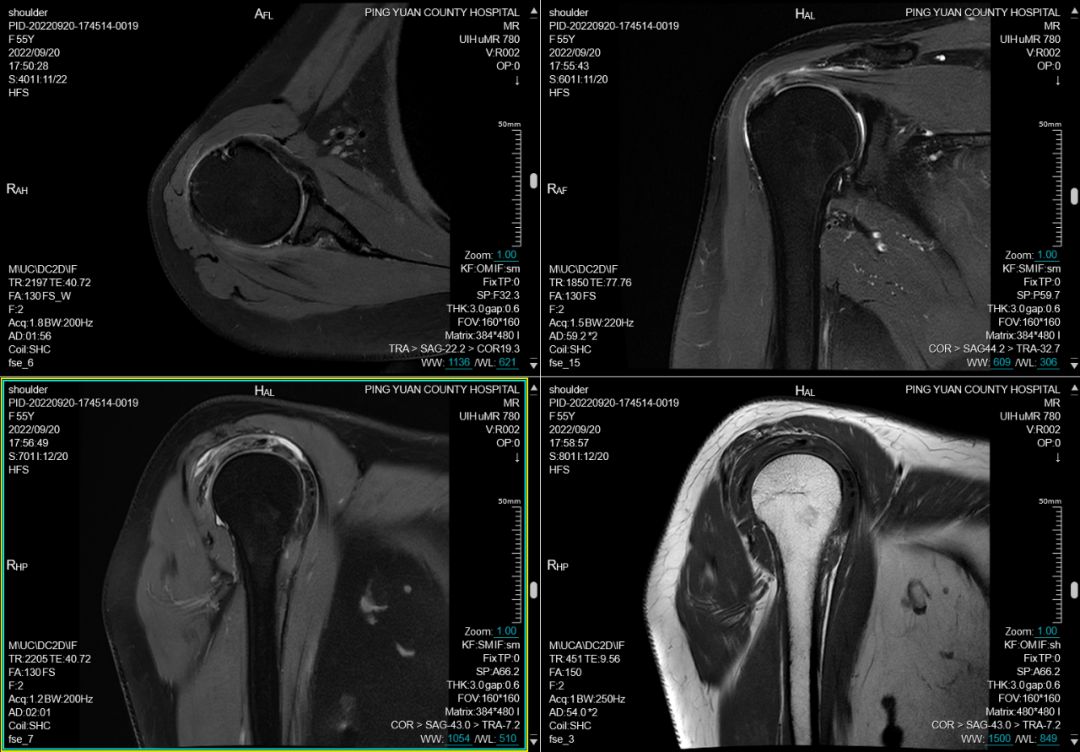

六、在四肢及关节检查方面:图像更清晰,后处理功能更丰富

MRI彻底变革了骨骼肌肉结构的成像,主要应用于创伤、关节炎、肿瘤和感染等方面。在创伤方面可显示平片或CT不能显示的病变如骨挫伤或骨小梁骨折,隐匿性骨折平片甚至CT易漏诊,而MRI能清晰显示。MRI是无创评估关节内软骨的最佳检查手段,能清晰观察软骨细微变化。

(肩关节平扫)